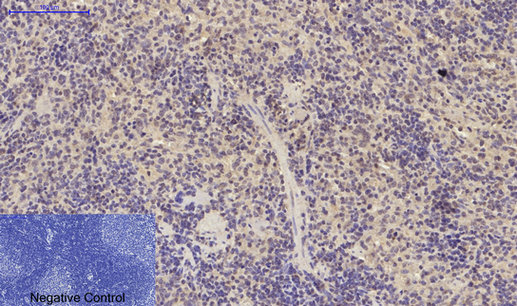

ARG66190 anti-Smad 2 antibody IHC-P image

Immunohistochemistry: Paraffin-embedded Mouse spleen tissue stained with ARG66190 anti-Smad 2 antibody at 1:200 dilution (4°C, overnight). Antigen Retrieval: Boil tissue section in Sodium citrate buffer (pH 6.0) for 20 min.

Negative control was used by secondary antibody only.